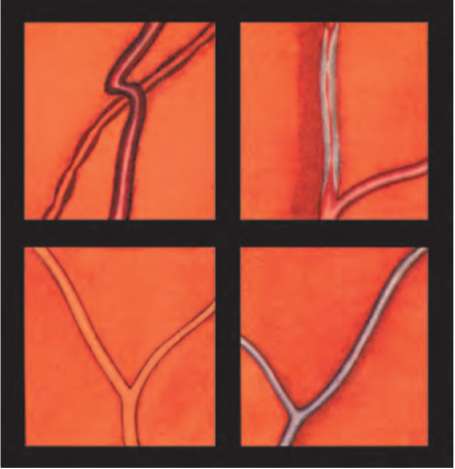

Рис. 20.4. Гипертонический ангиосклероз сетчатки. Симптомы медной и серебряной проволоки